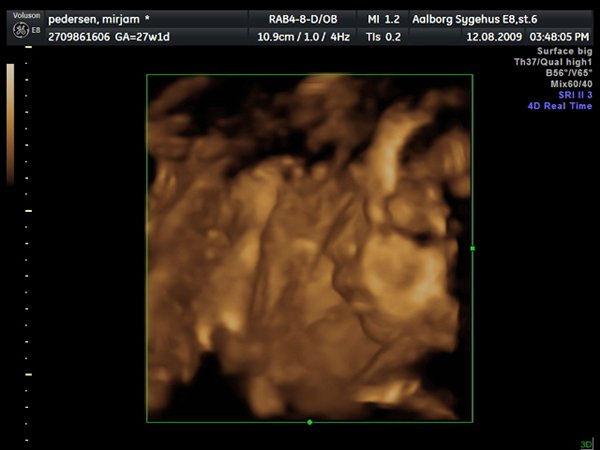

Så var jeg til 3D scanning, og det er en lille PRINSESSE

Hun var bestemt ikke samarbejds villig, vi skulle ihvertfald ikke bestemme hvordan hun sku ligge, så hun lå med hænderne oppe foran hovedet og somme tider med benene oppe foran os.. Så jeg fik rabat kom af med 800kr og han scannede mig ca 50 min. Han sagde hun vejede 990 gram

Vedhæftede fotos (klik for at se i fuld størrelse)